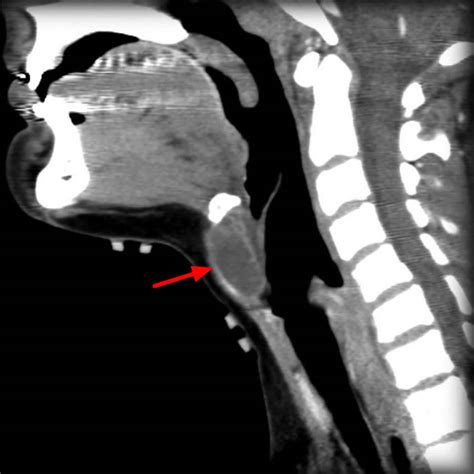

When a physician suspects a Duct Cyst Thyroglossal, they will perform a physical examination to check the cyst’s mobility and location. To confirm the diagnosis and rule out other conditions like lymphadenopathy or branchial cleft cysts, diagnostic imaging is generally required.

CT Scan Provides detailed anatomical mapping; often used to determine the extent of the cyst if infection is present.

During the Sistrunk procedure, the surgeon removes not only the cyst but also the middle portion of the hyoid bone and a tract of tissue extending to the base of the tongue. This comprehensive approach is vital because remnants of the thyroid duct often weave through or around these structures. By removing this entire “path,” surgeons significantly reduce the probability that the cyst will return.

The hallmark of a Duct Cyst Thyroglossal is a painless, smooth, and cystic mass situated along the midline of the neck. Because of its anatomical connection to the hyoid bone, the mass often moves upward when the patient swallows or protrudes their tongue. This movement is a critical diagnostic sign for clinicians.